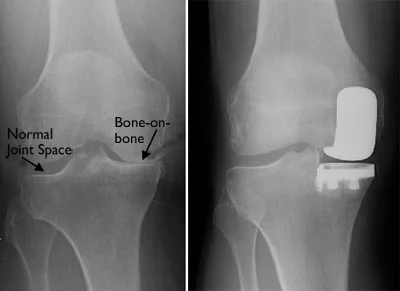

Partial Knee Replacement

Osteoarthritis sometimes occurs in just one of the three compartments of the knee (3). Surgeons can therefore perform a partial knee replacement.

The key advantage is that the majority of the knee is undamaged and untouched as a smaller incision is required (7-10cm). This procedure also has a faster rehabilitation process. The disadvantages are that partial knee surgery may not last as long as total knee replacement.

Arthritis affecting only the medial compartment (L) and x-ray showing a partial knee replacement (R)